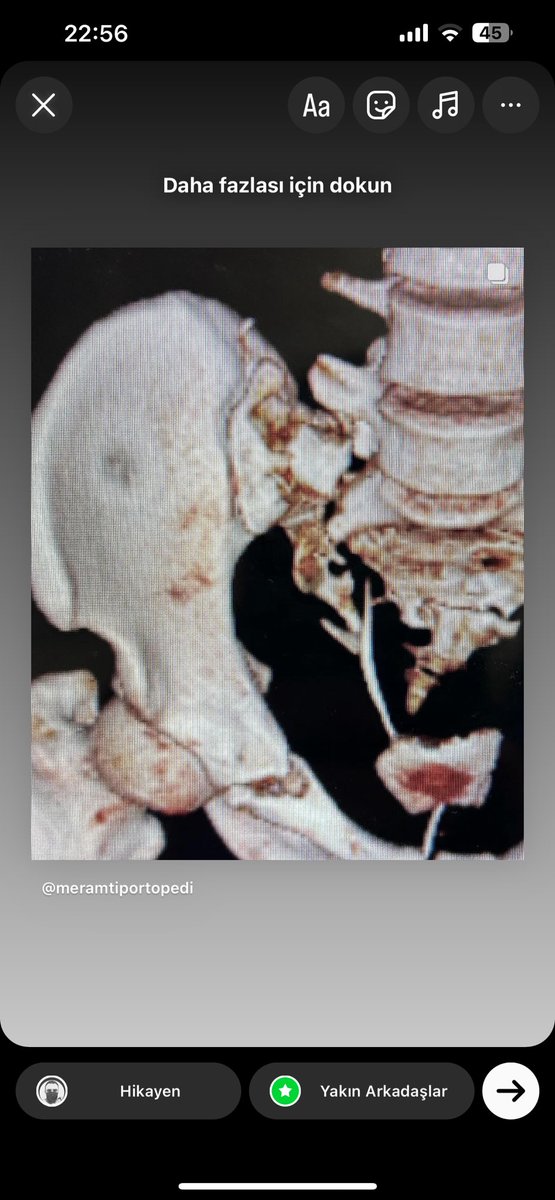

@radRounds Probably vertical shear pelvic injury. İt may be bilateral transforaminal or U/H type sacral fracture